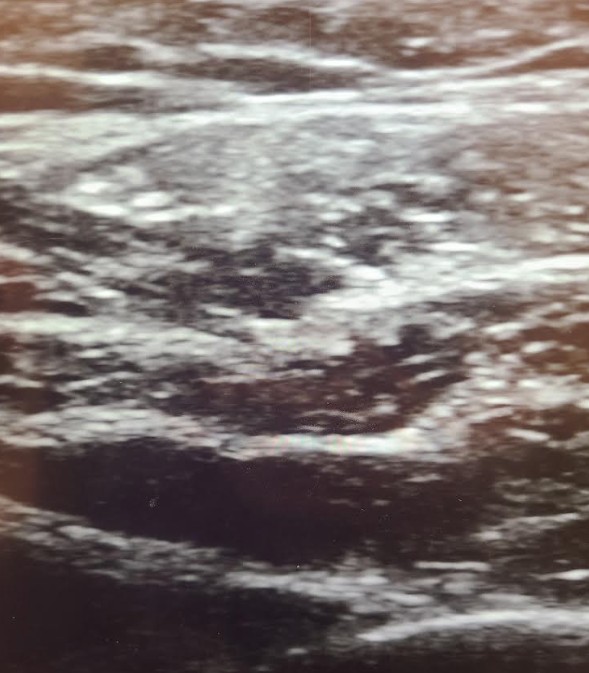

当院のこだわり:エコーで“咬筋3層”を評価し、層別にデザイン注入

咬筋は浅頭・中間層・深頭など多層構造で、層ごとに厚みや走行が異なります。

単一層だけを狙うと効きムラや過不足が出やすく、たるみ・コケのリスクも高まります。

- 超音波(エコー)ガイドで厚み・層・血管・下顎孔周辺を評価

- 層別・面状の少量分割で“効かせすぎ”を回避しつつ、自然なシャープ感を設計

- 口角・頬の下垂に配慮し、外側優位・安全域を基本にプランニング

- 準備:必要に応じて表面麻酔・エコーで層厚み確認